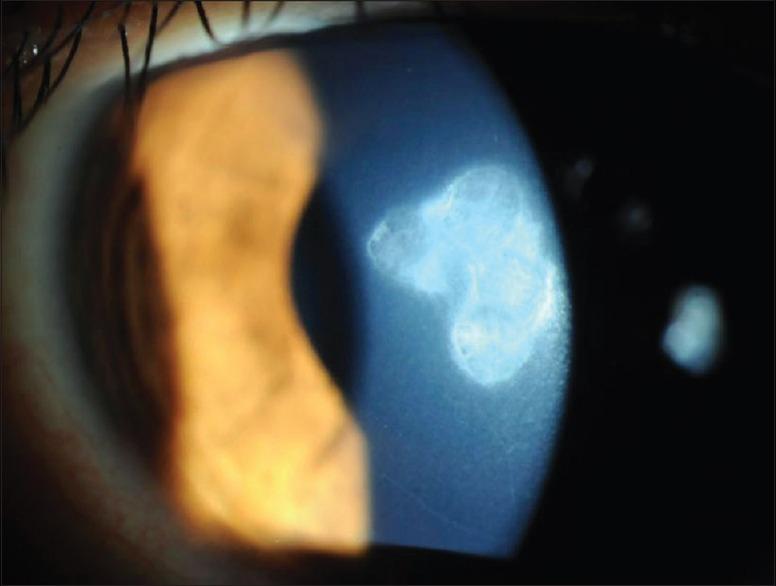

To report a rare case of infectious keratitis after collagen cross-linking (CXL) for keratoconus. A 20-year-old male patient underwent CXL for keratoconus in his right eye. Four weeks after the procedure, he reported blurred vision and redness with increasing pain in the treated eye. Ophthalmic examination revealed a corneal epithelial defect with corneal infiltrates that exhibited branching needle-like opacities. The patient was diagnosed with infectious crystalline keratopathy (ICK). Corneal scrapings and culture indicated the presence of . The patient was successfully treated with fortified vancomycin and ceftazidime over several weeks. ICK is a potential post-operative complication of CXL that can lead to corneal scarring with a permanent reduction in visual acuity.

报告一例圆锥角膜胶原交联(CXL)术后罕见的感染性角膜炎病例。一名20岁男性患者右眼接受了圆锥角膜CXL手术。术后四周,他报告患眼视力模糊、发红且疼痛加剧。眼科检查发现角膜上皮缺损,伴有角膜浸润,表现为分支状针样混浊。该患者被诊断为感染性结晶性角膜病变(ICK)。角膜刮片及培养显示存在…… 患者通过强化万古霉素和头孢他啶治疗数周后成功治愈。ICK是CXL术后一种可能导致角膜瘢痕形成并永久性降低视力的并发症。